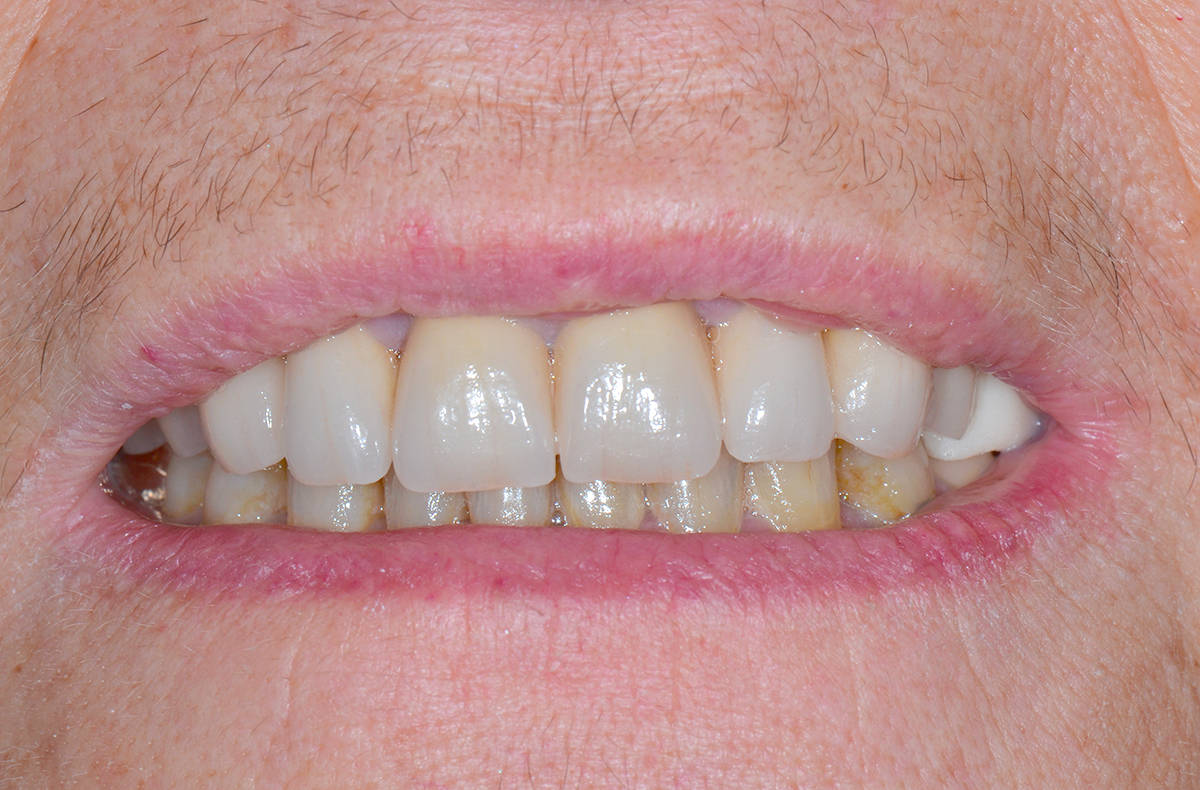

Patiente présentant des dents mobiles avec des migrations laisant apparaître des espaces. Un bridge céramique est réalisé de manière à supprimer les espaces et immobiliser les dents.